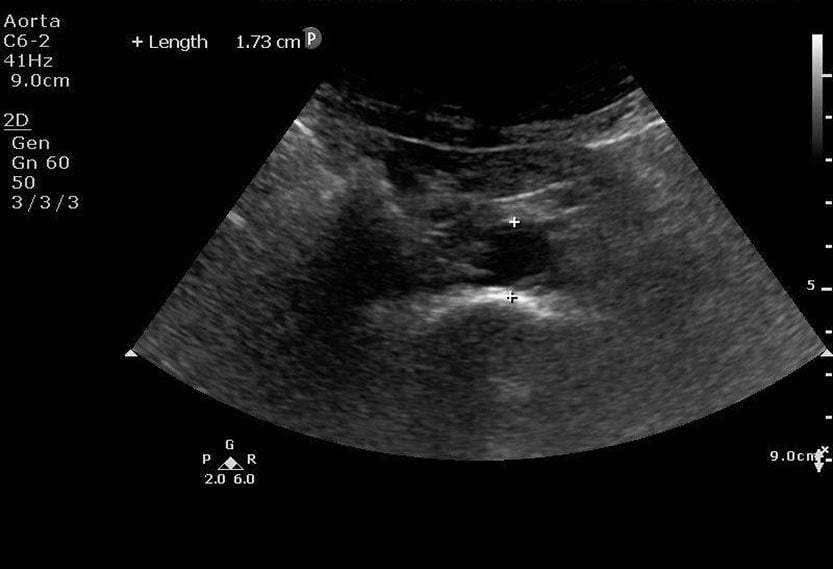

This is a 53 year old female who presents with altered mental status. She is found to have sepsis. Her urinalysis is marginally positive for infection. She is not fluid responsive and does not respond to pressor support. Hydronephrosis is discovered on bedside ultrasound resulting in urology consultation and operative management for source control.